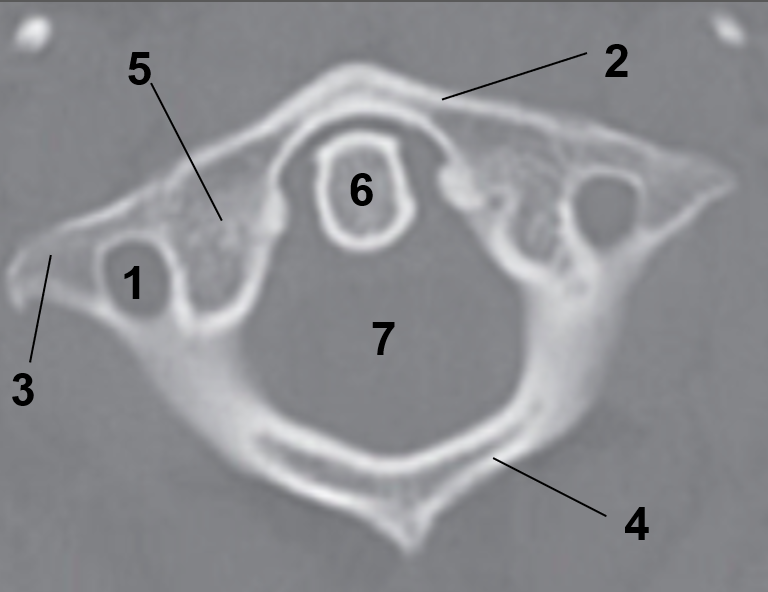

1?

Hard Palate

2?

Maxillary Bone

3?

Mandibular Rami

4?

Dens

5?

Transverse Foramen C1

6?

Spinal Cord

7?

Auricle

8?

Atlas